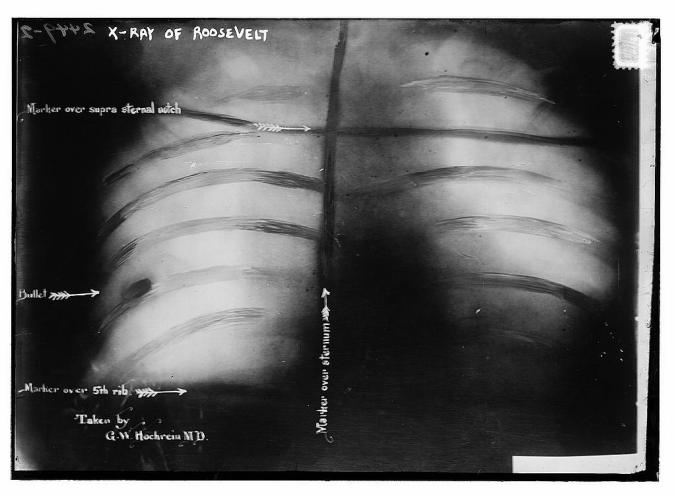

The bullet hit TR in the chest. The doctors later concluded that, had it not been for the eyeglasses case and 50-page typewritten speech stuffed in his inner coat pocket, the president would have been mortally wounded.

Roosevelt pulled a handkerchief from another pocket and coughed into it experimentally. Seeing no blood, he concluded the bullet didn’t hit his lung, and demanded to be taken to the auditorium.

When Roosevelt’s speech began to slur, his aides insisted he end his speech. TR was taken to a local hospital for emergency treatment, but when he went home eight days later, the bullet was still in his chest. It stayed there the rest of his life.